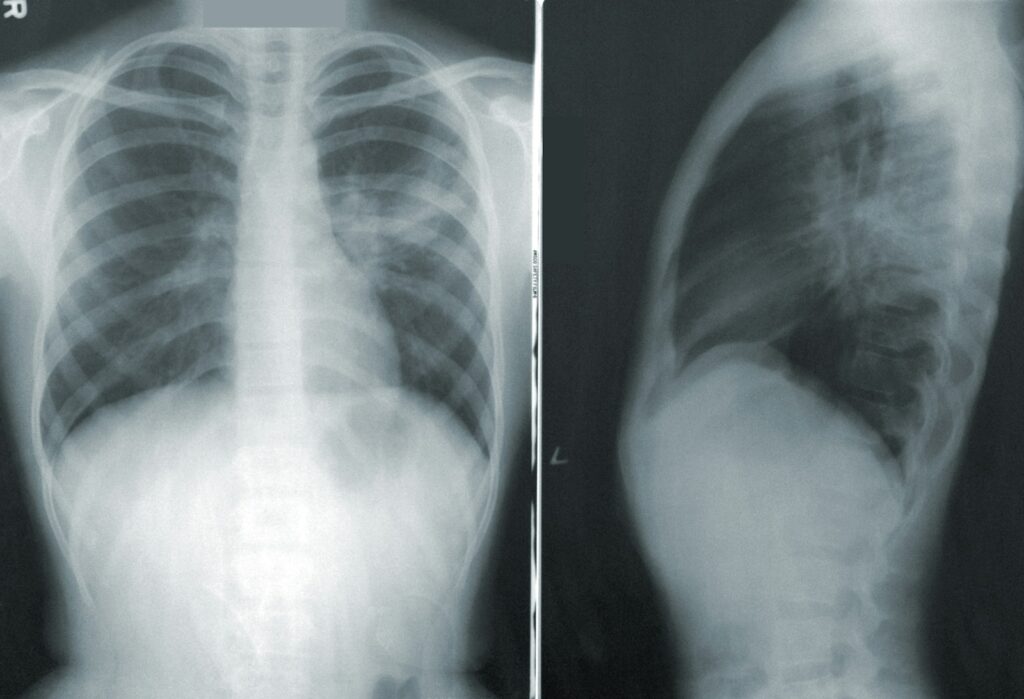

It wasn’t until a fateful day, against the backdrop of her daily commute in Fremont, California, that Denise’s perspective shifted dramatically. A billboard, featuring an African American female— a reflection of Denise herself— urging former smokers to get screened for lung cancer, caught her eye. This visual nudge, coupled with the personal connection she felt, prompted Denise to undergo a low-dose CT scan, a decision that would alter the course of her life. The scan unveiled an early, yet menacing tumor in her lung, plunging Denise into a whirlwind of emotions. The fear of facing her mortality and the daunting task of breaking the news to her family, especially her mother who had previously endured the agony of losing a spouse to cancer, weighed heavily on her.

The advancements in cancer treatments are paralleled by significant progress in screening technologies. The low-dose CT scan, recommended for current and former heavy smokers over the age of 50, has become a critical tool in detecting lung cancer at its earliest stages. Early detection is paramount, as it substantially increases the chances of successful treatment and survival. Yet, the uptake of screening remains alarmingly low, with only a fraction of those eligible undergoing the annual scans. This gap highlights the urgent need to demystify and promote lung cancer screening, especially given its potential to save lives.